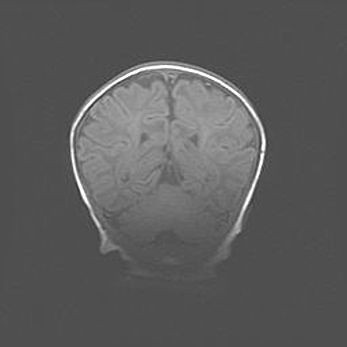

Открытая гидроцефалия.

Возраст: 9 месяцев 12 дней

Вес: 6800 г

Пол: мужской

Окружность головы: 41,5 см

Срок гестации: 28 недель

Гидроцефалия головного мозга у новорожденных имеет характерный признак: опережающий рост окружности головы приводит к визуально хорошо определяемой гидроцефальной форме сильно увеличенного в объёме черепа. Детские неврологи определяют следующие симптомы гидроцефалии у грудничков: выбухающий напряжённый родничок, частое запрокидывание головы, смещение глазных яблок к низу.